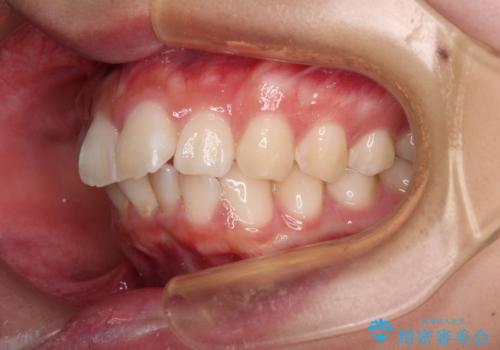

- 前歯部のデコボコと口元が出ているのが気になるとのことで来院された患者様です。

口元の突出感の解消と、このままデコボコを解消するとさらに出っ歯傾向になってしまうことを考慮し、上下左右の小臼歯を抜歯しクリアブラケットにて矯正していくこととしました。

舌突出癖を改善するトレーニングを一生懸命やっていただいたおかげで2年以内に治療を終えることができました。